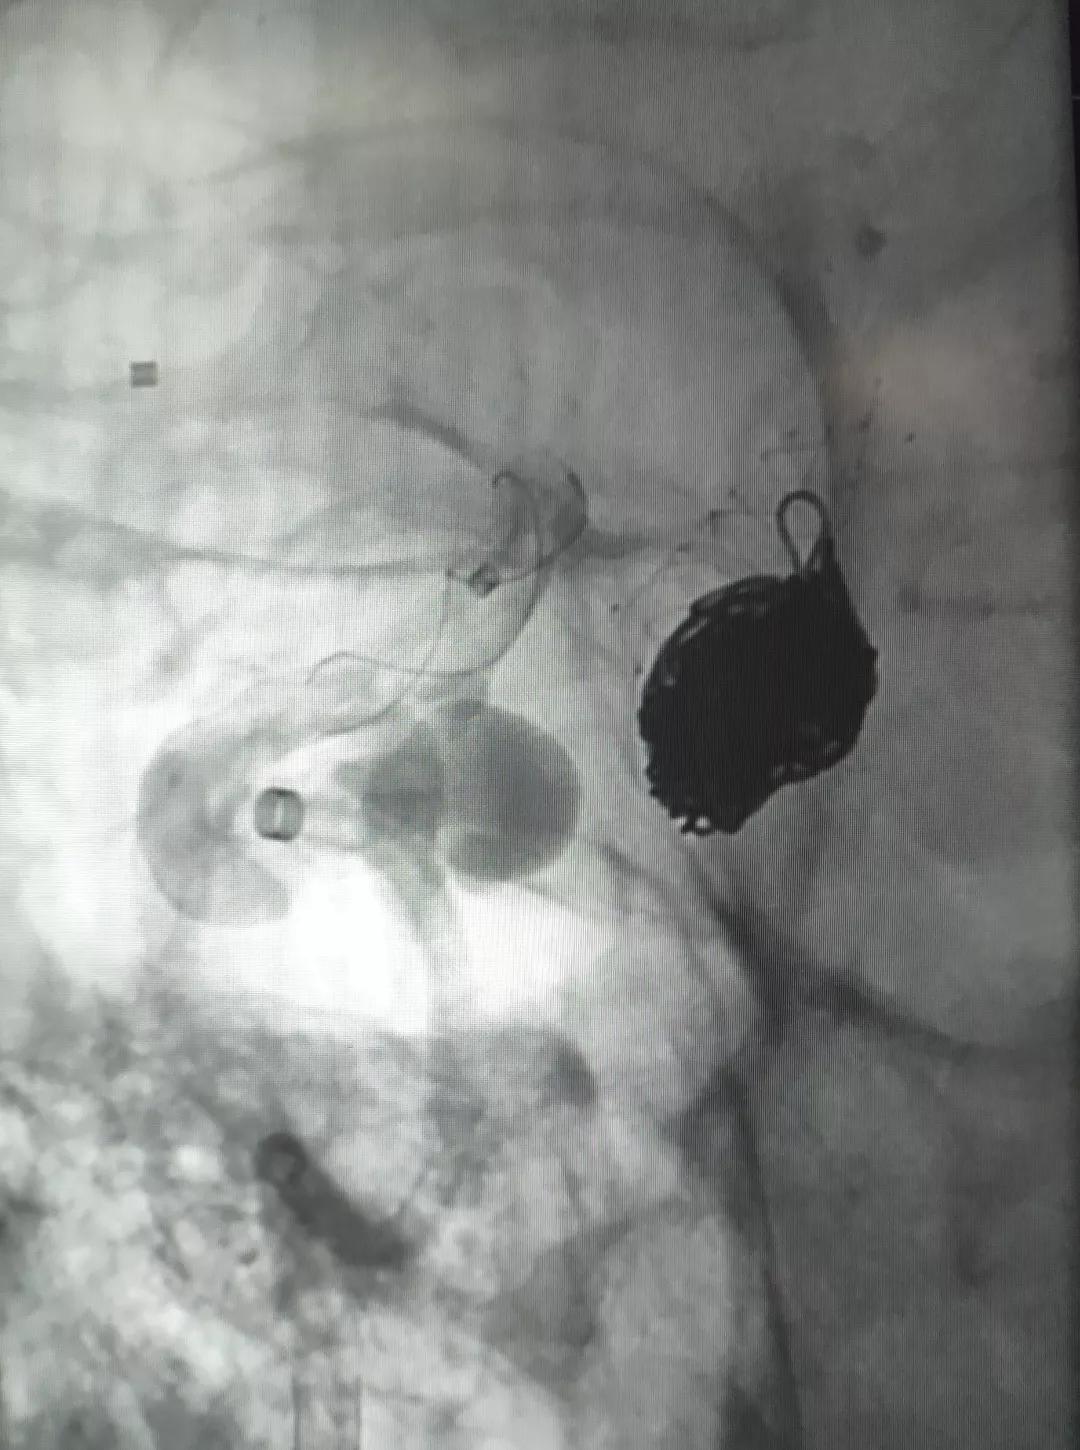

▲造影见造影剂滞留,载瘤动脉通畅。